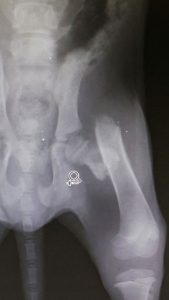

Besleme bölgemizden araba çarpması ihbarı ile gelen yavru köpeğimiz klinikte tedavi altına alındı. Çekilen röntgen sonucunda vücudunda kırık tespit edildi ve ameliyatı geçekleştirildi. İyileşme süreci tamamlandığında yaşadığı bölgeye bırakılacak.

Güncelleme: Yavru köpeğimiz maalesef melek oldu.